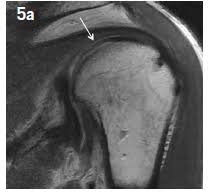

An upright mri allows patients to be scanned while standing or sitting, which can be helpful in diagnosing certain conditions. Does it seem you have no choice in where you go and what you pay for a radiology procedure? Private physios, paying for mri scans & torn shoulder problems. Estimate the cost of your mri or ct scan at american health imaging with our simple calculator. However, there are also alternatives such as ultrasound, which can also confirm rotator cuff tears.

Estimate the cost of your mri or ct scan at american health imaging with our simple calculator. $800 pesos ($43.24 usd) mri of lumbar spine without dye: Super angebote für mri procedure hier im preisvergleich. Rotator cuff tears can often be diagnosed by physical examination, but cannot be confirmed without imaging. A mri in salt lake city costs $890 on average when you take the median of the 17 medical providers who perform mri procedures in salt lake city, ut. Average prices are for mri procedures performed at honorhealth facilities around the valley, and do not include physicians' fees. When i called one facility, they told me the mri i described would cost $1,600. In different conditions, the cost for even just one mri scan can surpass $13,000. They can range from $300 to $9000. Mri spine cervical w/o cont. I went to my gp after about 6 weeks of shoulder pain who said i'd torn something in my shoulder & referred me to physio, who i saw today. Please contact your physician's office and health insurance provider directly for price information. Our experienced staff are friendly and approachable, and can answer any.

Estimate the cost of your mri or ct scan at american health imaging with our simple calculator. Please contact your physician's office and health insurance provider directly for price information. How much does an mri cost? If patients have not hit their deductible, that money comes straight. Surgeries / operations (head & torso) The cost of an mri will vary greatly between inpatientand outpatient facilities. How much does an mri cost? Those on high deductible health plans or without insurance can save when they buy their procedure upfront through mdsave. Although they may not say so, some physicians in health care systems or hospital groups are contracted with hospitals. If a person receives an mri scan at the. Our experienced staff are friendly and approachable, and can answer any. A shoulder mri is done to check a shoulder for arthritis, bone tumors, torn ligaments or tendons, and other similar problems. Read more about how mdsave works.